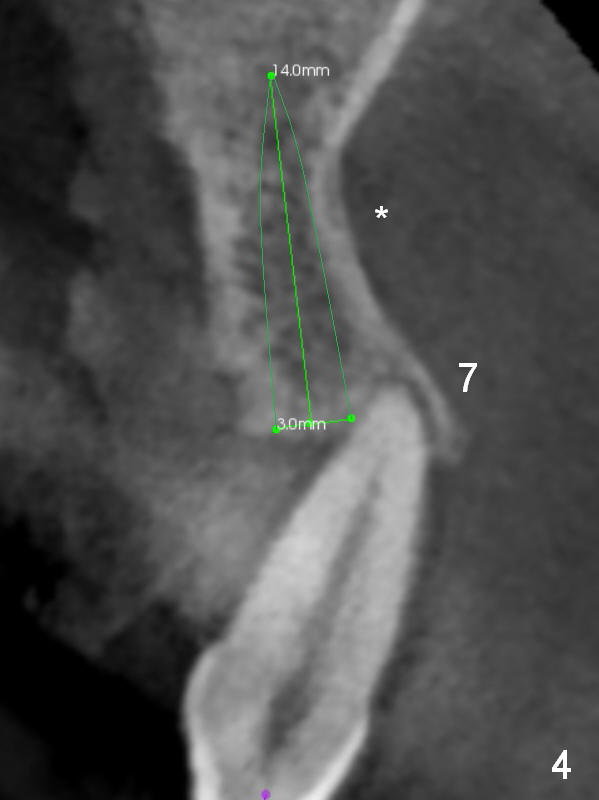

The bone width at #9 is narrow (Fig.3, as compared to Fig.2 for #8). Prepare SM (straight) and Tatum (angled) 1-piece implants. Try to place a 2-piece implant at #10 if possible (Fig.5, compare to Fig.4) so that FPDs and crowns can be converted to hybrid denture in the future.

In case primary stability is questionable for example at #15 (Fig.10), consider placing implants at #12 and/or 14 (Fig.7,9).